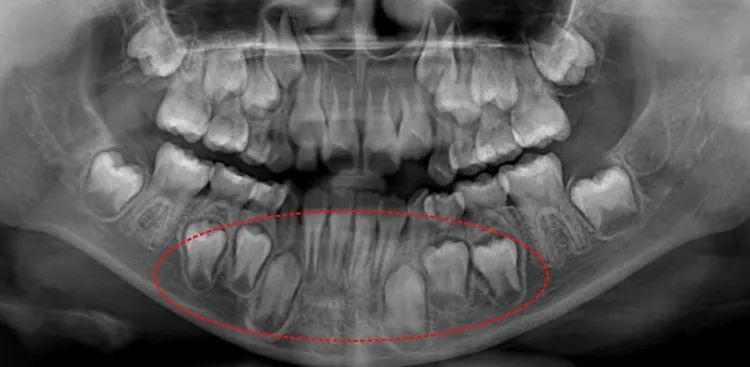

比如观察儿童牙齿的生长情况。如发现埋伏牙、多生牙、阻生牙等异常情况可以及时处理,避免恒牙萌出后长得“七扭八歪”,影响颜面发育。